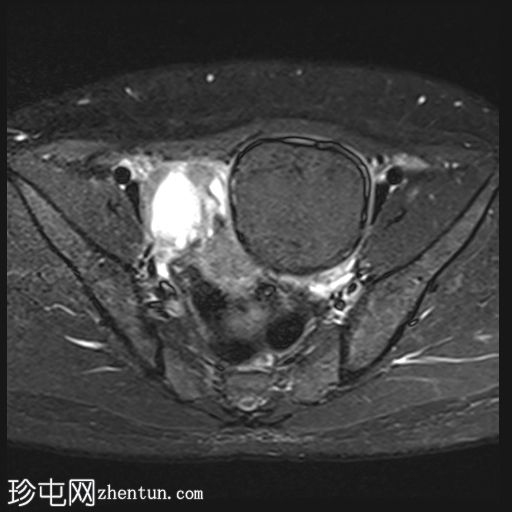

轴位

T1加权像

左侧卵巢可见一巨大、无强化囊性病变。该病变壁薄,在T1加权像和T1脂肪抑制像上呈均匀高信号,在T2加权像上呈独特的阴影状,符合子宫内膜异位囊肿的特征。值得注意的是,该病变可见两个增强灶,但未见内部实性成分或对比增强。

此外,右侧卵巢内数个小的、无强化囊性病变表现出类似的信号特征,这也符合子宫内膜异位囊肿的特征。

右侧卵巢内还有另一个囊性病变,在T1加权像上呈低信号,在T2加权像上呈高信号,并可见液平面。该病变无对比剂强化,可能代表出血性黄体囊肿。

双侧卵巢向内侧移位,形成“接吻卵巢征”。